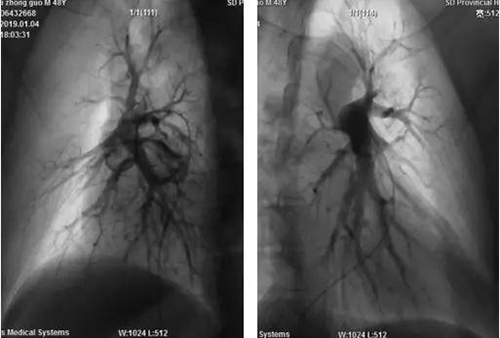

一例48岁低氧血症患者的左右肺动脉造影